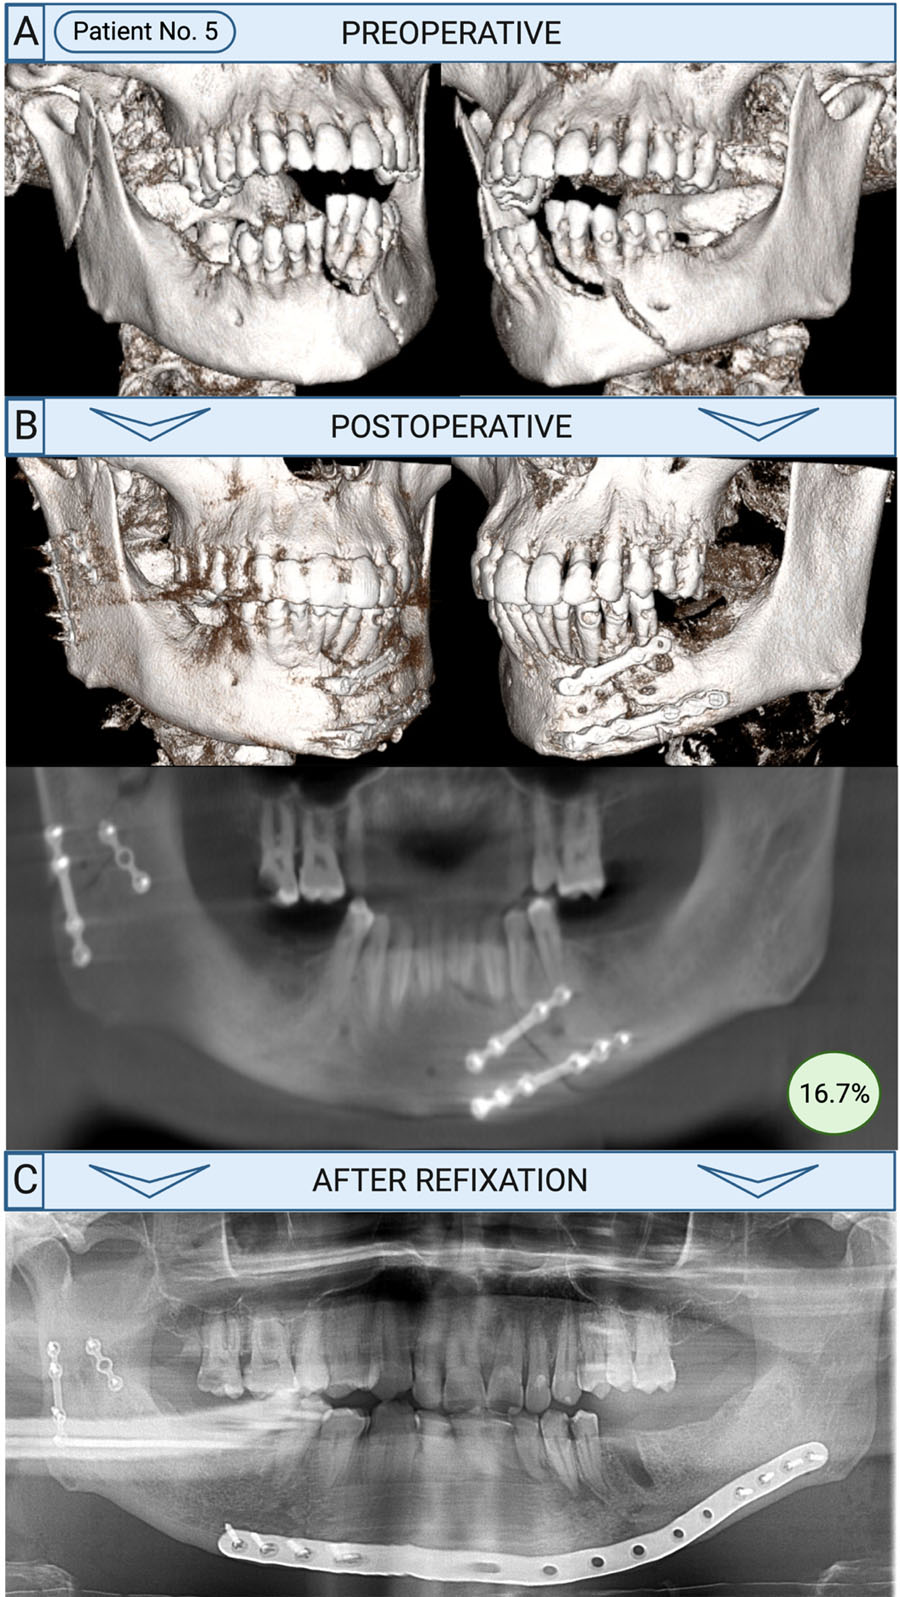

Known risk factors include smoking, alcohol use, drug abuse, and immunosuppression. In our cohort, 64.7% of patients needing refixation had at least one of these factors. However, 35.3% had none—prompting a deeper evaluation. Among these, several patients were found to have received substandard surgical care. To assess this, we reviewed the 17 cases as part of a larger, blinded study using AO surgical principles. In 5 of the 6 patients without recognized risk factors, surgical quality was deemed inadequate—with full agreement among specialists in 3 cases. Our findings underscore not only the relevance of established risk factors but also the critical role of high-quality surgical care in preventing complications.

How was refixation performed?

Refixation was typically prompted by complications such as osteomyelitis or non-union, both of which demanded more invasive surgical approaches. In 82% of cases, an extraoral approach was used, employing load-bearing osteosynthesis techniques. Reconstruction plates were the most common fixation method—47% involved conventional plates, while 41% utilized patient-specific, 3D-printed plates.

Bone grafting from the iliac crest was necessary in about 30% of cases. Intraoral soft tissue conditions likely played a role in the surgical decision-making process, as successful grafting depends heavily on infection-free closure and adequate healing.

On average, refixation was performed 3.5 months after the initial surgery, ranging from 1 to 9 months—consistent with typical bone healing timelines. Patients who could be managed with hardware removal alone were excluded from this study. In some cases, intraoperative evaluation during revision may have revealed sufficient bone healing, negating the need for full refixation. Therefore, refixation was reserved for cases with substantial complications and inadequate osseous healing.